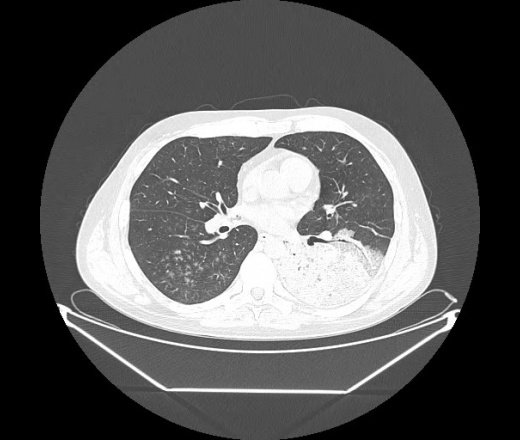

М. 1984 г.р.  Лихорадка 39, кашель , одышка.. и надоевший всем вопрос- "типично ли для ковид?" ( в настоящее время на него обязательно нужно дать ответ в своем протоколе)

На мой взгляд нетипично для ковид: много центрально-расположенных поражений, лобарное поражение нижней доли слева. 50/50

Не типичая картина для ковид.

КТ-признаки двусторонней бактериальной пневмонии.

Все верно, здесь абсолютно нетипичная картина, несмотря на матовое стекло с ретикулярными изменениями, но почему-то  посчитали иначе. Кстати,  "малыша" не заметили)?